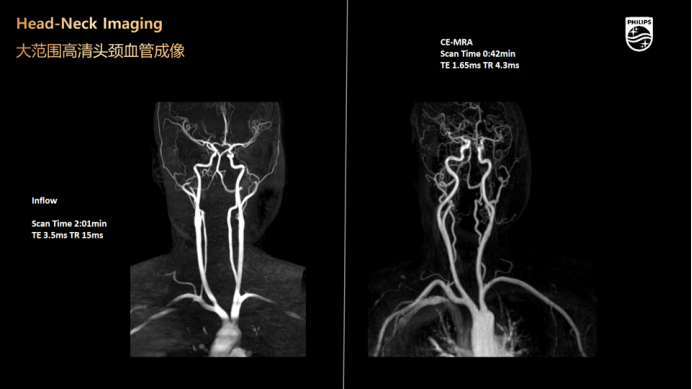

不打药动脉成像

3.0磁共振全新推出的不打药头颈部动脉、肾动脉、冠状动脉成像技术可以安全无创的完成动脉成像,为临床提供准确的诊断信息。对于孕妇、儿童、造影剂敏感的患者来说,这种方式更安全,应用范围更广、检查时间更短。